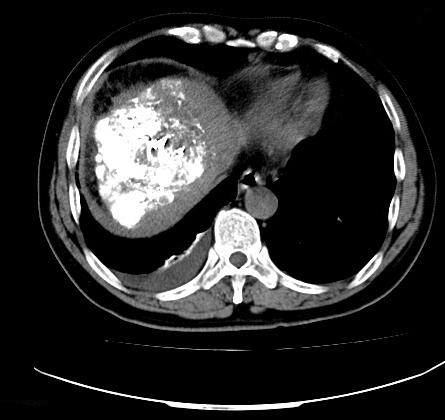

58岁的马先生(化名)凌晨突发腹痛来院就诊。CT 示患者肝右叶多发病变,B超示腹腔内大量积液,接诊医生考虑患者为肝癌伴破裂。此时患者已失血性休克。在开放四条静脉通路,连续快速补液2000-3000ml的情况下,患者血压仍只有90/60mmHg。患者被迅速送往手术室开展治疗。

术中介入与血管外科王卫国主任、戴正行副主任当机立断,在局麻观察下行肝动脉造影和栓塞术,经过一个多小时的努力,终于止住了出血,患者的生命体征渐趋平稳。